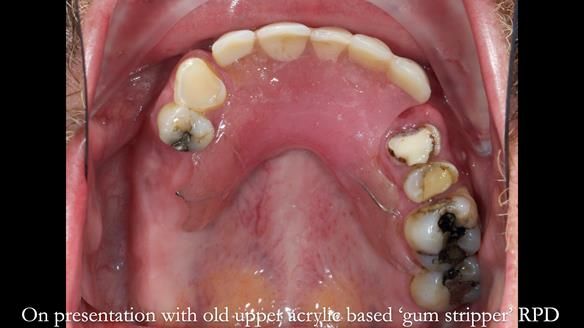

Keith’s case was one of the most challenging and rewarding cases I’ve treated this year. This 64 year old man presented with ill-fitting acrylic partial dentures that lacked stability, retention, and aesthetics. They constantly broke. He had lost the upper front teeth in a road traffic accident in his early 20s. The unopposed teeth had erupted, taking up space. After careful planning, we made a durable, metal-based upper partial denture/splint to address his dental concerns. He loved the outcome.

1. Denture design: A custom cobalt-chromium framework was Scandinavian-designed to maximise stability, protect the remaining teeth, and allow for future additions if needed.

Keith’s denture incorporated a Duracetal shell clasp on upper right first premolar (Myerson), which are designed to be virtually visible, providing a more aesthetic solution while enhancing patient comfort. The Scandinavian-inspired approach, based in modern removable prosthodontic techniques, ensured the denture was not only durable but also visually pleasing. Additionally, the design was carefully planned to allow for future modifications, ensuring that if Keith loses additional teeth, the denture can be adapted rather than replaced entirely.